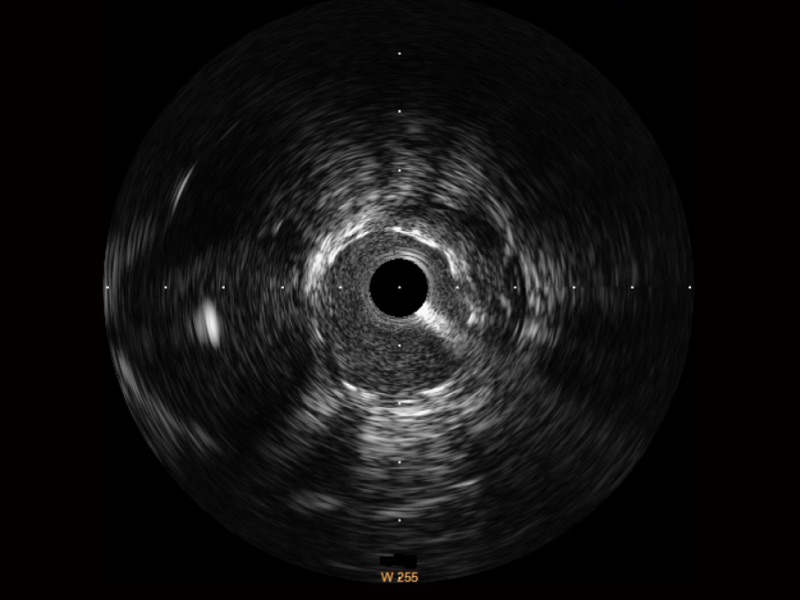

公海贵宾会员检测中心宽频IVUS图像

传统IVUS图像

对比传统IVUS导管成像,公海贵宾会员检测中心宽频IVUS图像的近场支架梁显影更细腻,远场中膜外血管仍清晰可辨,兼顾远中近,兼顾分辨力与穿透深度